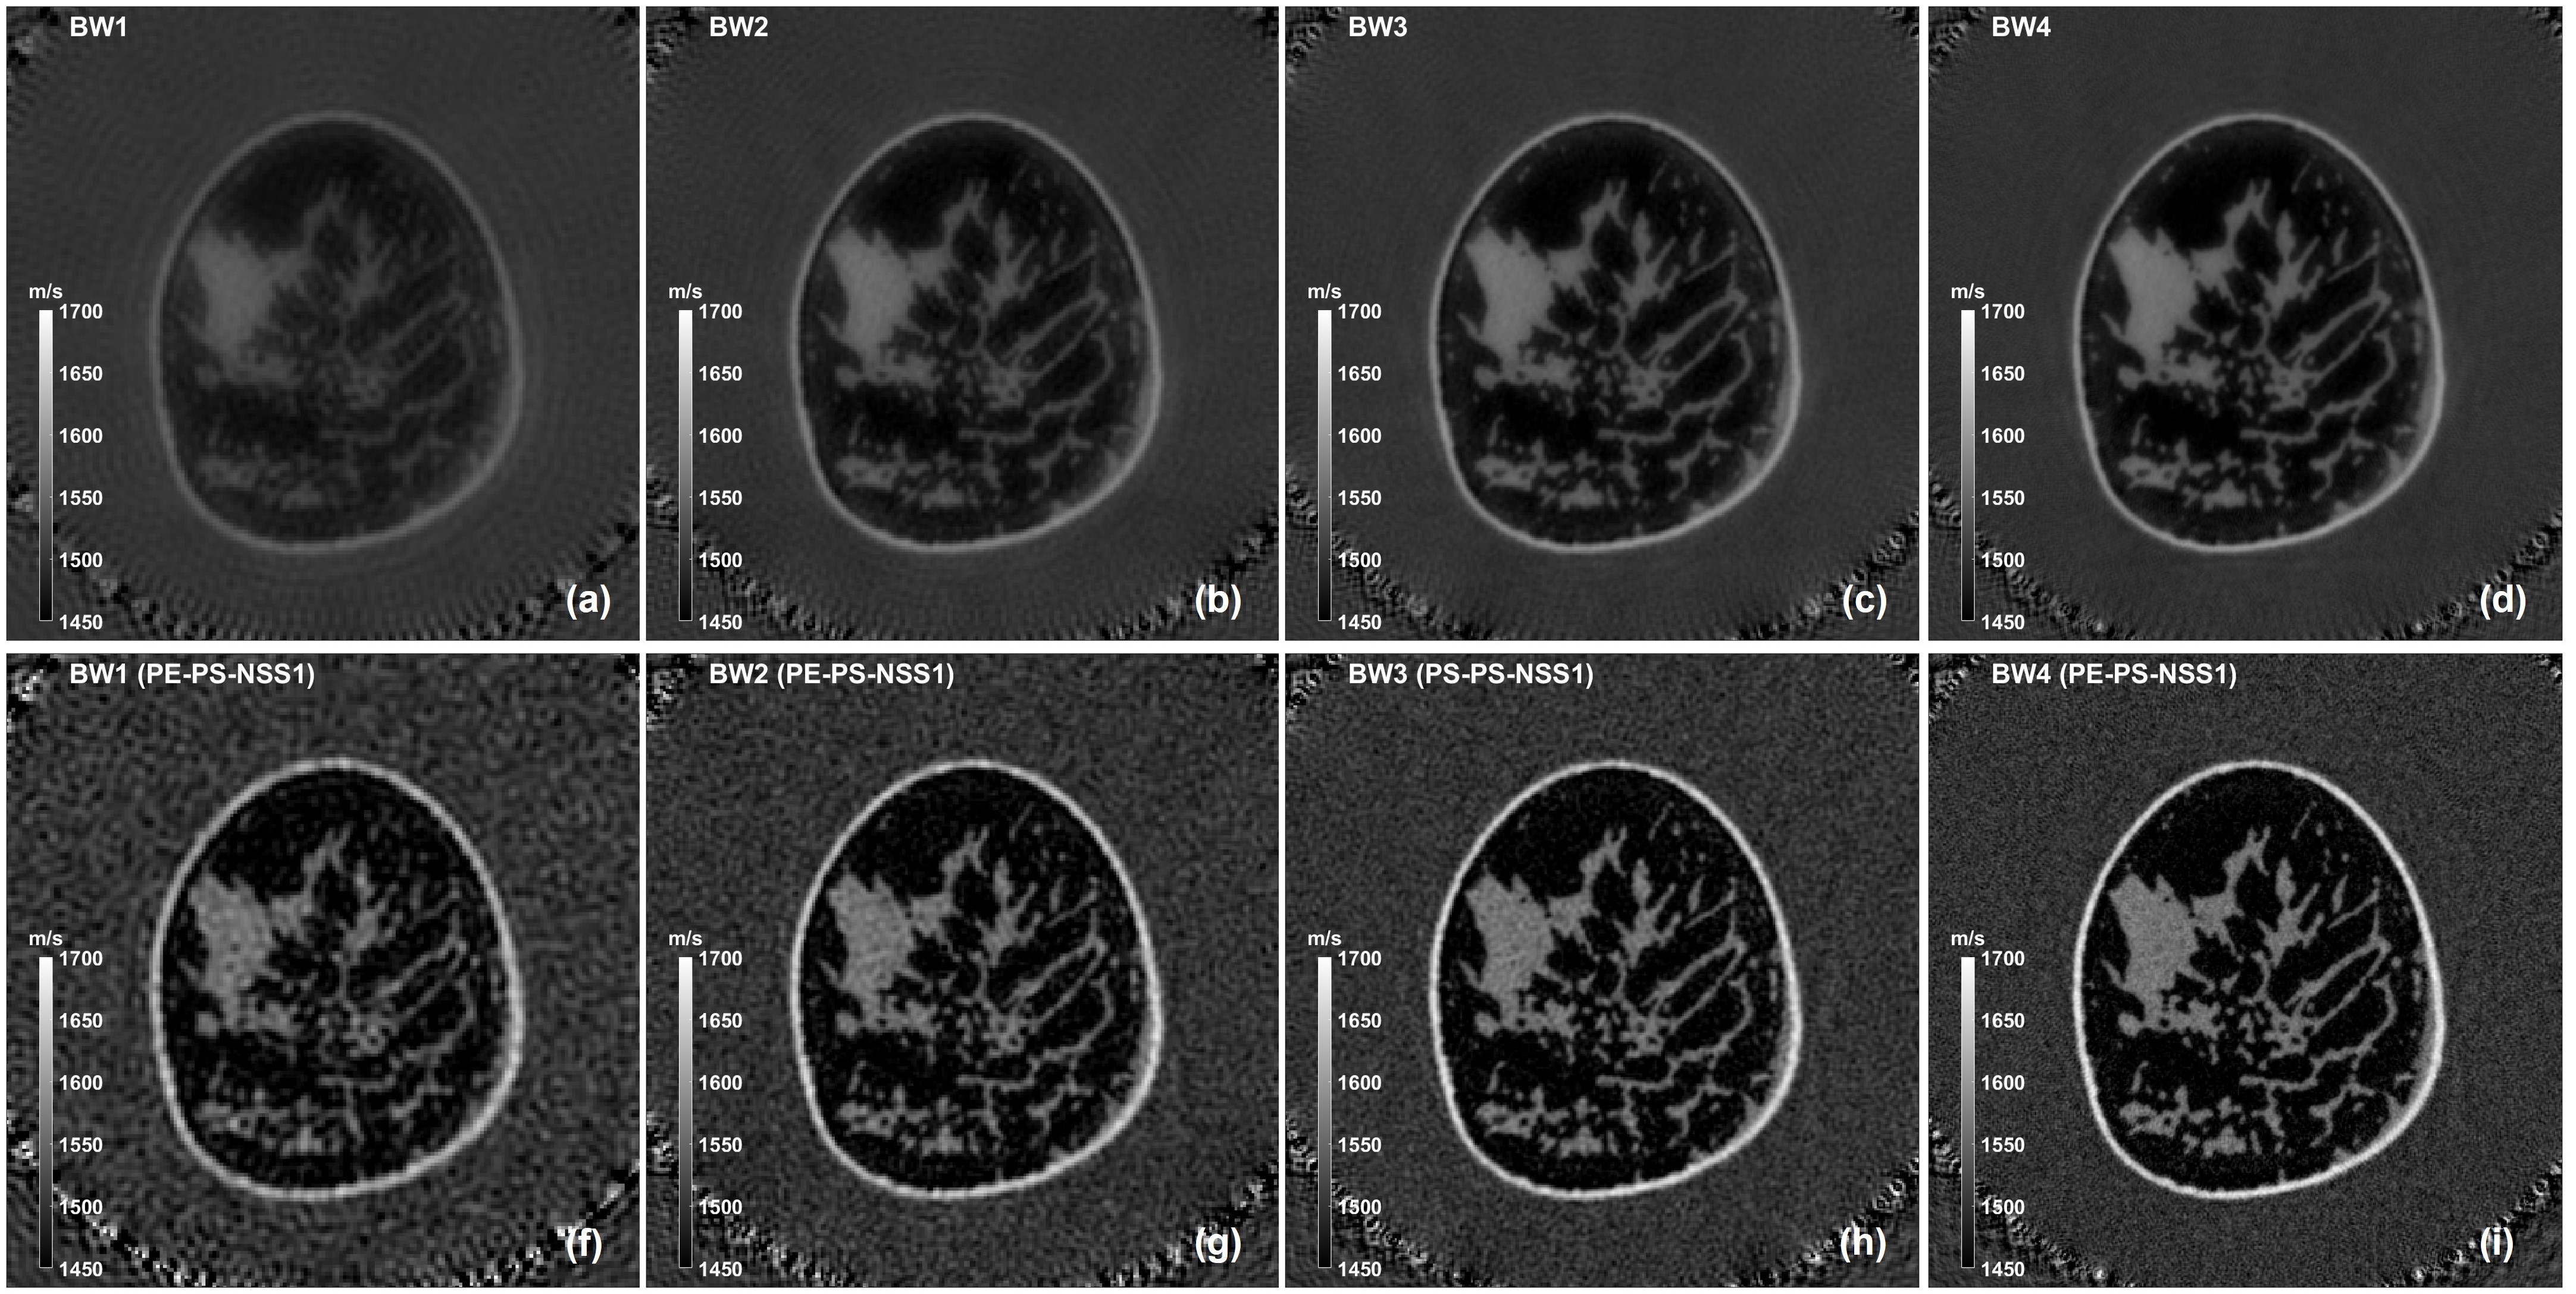

100-200 kHz (BW1) 280 x 280 1 mm TD2D, TD3D, Experimental Data

300 kHz (BW2) 350 x 350 0.8 mm TD2D, TD3D, Experimental Data

400 kHz (BW3) 466 x 466 0.6 mm TD2D, TD3D, Experimental Data

500-600-700 kHz (BW4) 700 x 700 0.4 mm TD2D, TD3D, Experimental Data

800-900-1000 kHz (BW5) 875 x 875 0.32 mm TD2D, TD3D, Experimental Data

Detailed description of the experimental data, including recommended data quality pre-processing, is given in [30]. The raw dataset is a time-domain real variable of size 2112 x 512 x 512; time series are sampled at 12 MHz. Frequency domain samples are obtained with a standard FFT after zero-padding the raw data from 2112 samples to 2400 samples. This operation creates a frequency bin of 5 kHz and allows to extract the discrete frequencies from 100 kHz to 1000 kHz at the corresponding interpolated bins. The frequency domain dataset has a size of 10 x 512 x 512 complex samples. Deterministic and stochastic inversions are initially run exactly as in the previous section (TD3D-FD2D). The initial velocity model is a homogeneous map (1480 m/s), known because the temperature of the water bath is monitored. The Cartesian coordinates of the array elements are also known (these can be measured during the fabrication phase of the array). Results are shown in Fig. 9 for a malignant mass and in Fig. 11 for a cyst. For both inversions, the reconstruction in BW1 shows poor image quality due to lack of sufficient SNR in BW1, Fig. 9 (e)(f) and Fig. 11 (e)(f). The deterministic reconstructions with windowed data, Fig. 9 (a) and Fig. 11 (a), show comparable image quality to the stochastic reconstructions with multiple super shots and multiple stochastic ensembles (Nss=64,NPE=1N_{ss}=64,N_{PE}=1 and Nss=16,NPE=4N_{ss}=16,N_{PE}=4 respectively), Fig. 9 (b)(c) and Fig. 11 (b)(c). The stochastic reconstruction with one super shot and multiple stochastic ensembles (Nss=1,NPE=64N_{ss}=1,N_{PE}=64), Fig. 9 (d) and Fig. 11 (d), shows inferior image quality, as also evidenced by the graph of the cost function. Finally, all reconstructions are re-run inverting sequentially at a single-frequency, from 300 kHz to 1 MHz in steps of 100 kHz (preserving the multi-scale approach with the number of pixels and the pixel value as in Table 2). This results into a higher number of speed of sound iterations, that explains improved image quality in Fig. 10 and Fig. 12. Results are unchanged, in particular: the stochastic reconstruction with one super-shot only has inferior image quality (again confirmed by the graph of the cost function), Fig. 10 (d) and Fig. 12 (d), the two stochastic reconstructions with multiple super-shots and multiple stochastic ensembles (Nss=64,NPE=1N_{ss}=64,N_{PE}=1 and Nss=16,NPE=4N_{ss}=16,N_{PE}=4 respectively), Fig. 10 (b)(c) and Fig. 12 (b)(c), show very similar image quality between them and when compared against the deterministic reconstruction, Fig. 10 (a) and Fig. 12 (a). In all the aforementioned cases, the cost functions of the two stochastic reconstructions employing multiple super-shots and multiple stochastic ensembles track each other, and both track the cost function of the deterministic reconstruction. Overall, when displayed on the 1350-1600 m/s range, image quality and anatomy are comparable to the ones published in [30].